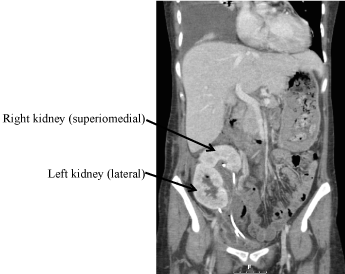

The right and left kidneys were transplanted en-bloc with the donor aorta and inferior vena cava (IVC). The donor aorta was anastomosed end-to-end onto the right internal iliac artery. The donor IVC was anastomosed end-to-side onto the right external iliac vein. The right kidney lay superio-medially in relation to the left kidney, which lay laterally (Figure 1). Both kidneys perfused well after a cold ischemic time (CIT) of 20 hours and an implantation time of 28 minutes. The donor ureters were anastomosed separately to the recipient's bladder using a modified Lich-Gregoir technique. Ureteric stents were left in-situ.

Figure 1: Intra-operative photograph: Dual en-bloc kidneys after implantation Right and left kidney measured 5.0 cm, with donor aorta (marked with black arrow) and inferior vena cava. Anastomoses to right internal iliac artery and right external iliac vein (controlled with blue sling), respectively.  View Figure 1